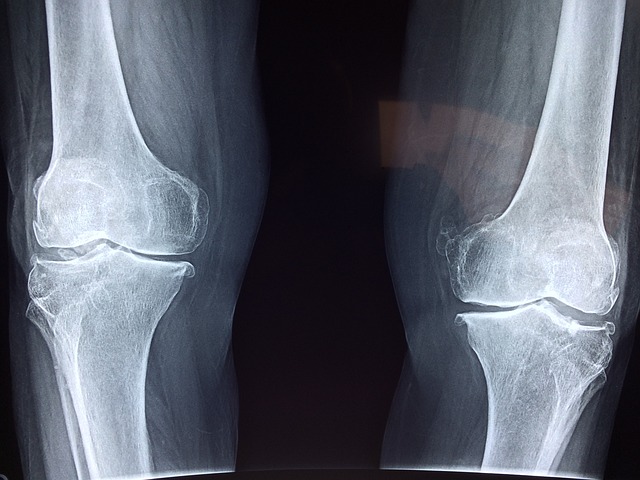

무릎 관절이 안 좋은 이유

3. 관절염

퇴행성 관절염과 류마티스 관절염은 증상이 비슷하지만 원인과 치료법이 다릅니다.

관절 통증이 4-6주 이상 지속되면 전문의 진단을 받는 것이 좋습니다.